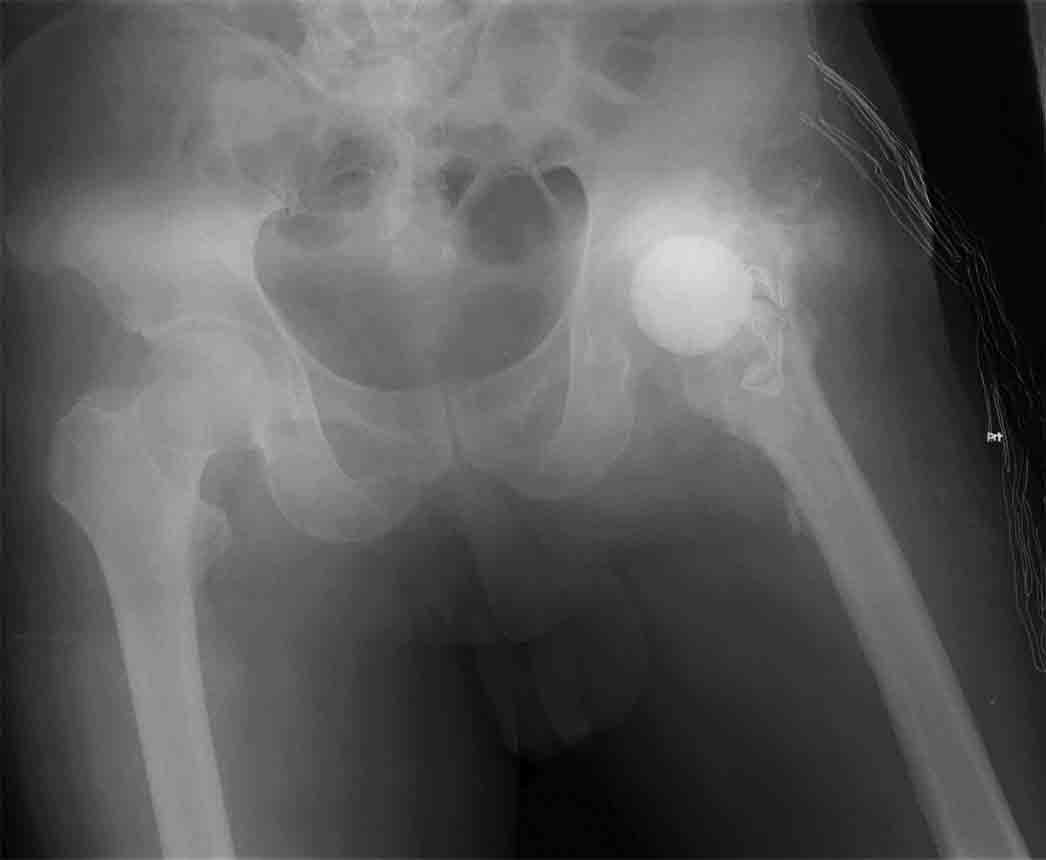

髋关节感染后的初次全髋关节置换术

患者55岁,男,股骨颈骨折内固定手术后感染3年,伤口窦道形成,股骨头已经大部吸收,有死骨.曾诊断为骨髓炎.我们首先一期进行髋关节感染后病灶清除,清除死骨肉芽和股骨头.用自制的抗菌素万古霉素骨水泥球作为填充器,放置在头臼位置,一期关闭伤口.伤口愈合.6个月后,检查血沉CRP血象正常激发实验阴性,进行初次全髋关节置换术.手术成功.感染无复发,功能良好.

用自制的抗菌素万古霉素骨水泥球作为填充器,放置在头臼位置

进行初次全髋关节置换术.手术成功